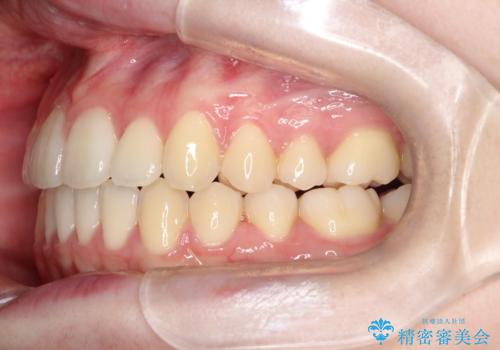

- 前歯のガタガタを主訴に来院されました。

開咬ぎみであったため、しっかりと前歯が噛むように計画を立てて治療をおこないました。

仕上がりも良く、患者様にも満足していただきました。

インビザラインは前歯を噛ませるような開咬の治療も得意としています。